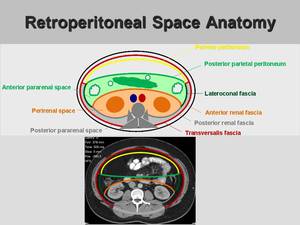

anterior pararenal space에 위치하는 것으로 생각된다.

후복강 낭성 종양에는 다음과 같은 것들이 있고 CT 특징을 통한 진단적 접근을 계획하였다.